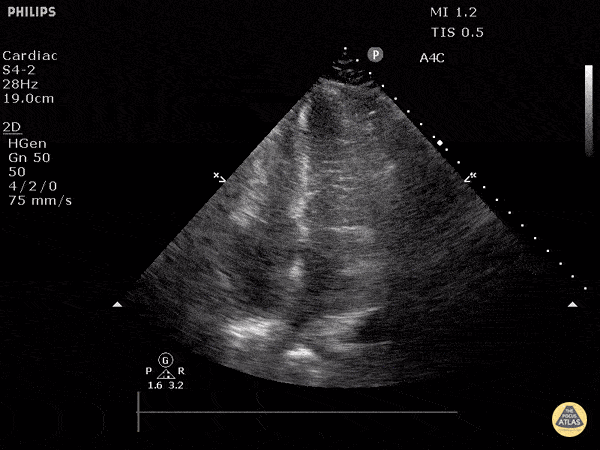

Apikal dört boşluk

Sol ventrikül fonksiyonunun değerlendirilmesi

Sol ventrikül (LV) fonksiyonu dört pencerenin tamamında değerlendirilebilir; ancak genellikle parasternal uzun aks görüntüsünde en kolay şekilde incelenir. Değerlendirme iki şekilde yapılabilir:

Görsel (subjektif) tahmin

EPSS (End Point Septal Separation) ölçümü

Çok sayıda çalışma, acil hekimleri ile kardiyologlar arasında global kardiyak fonksiyonun görsel değerlendirilmesi açısından yeterli uyum olduğunu göstermiştir.

RUSH muayenesinde genellikle ejeksiyon fraksiyonunun tam yüzdesine odaklanmak yerine, sol ventrikül fonksiyonunu geniş kategoriler halinde sınıflandırırız:

Hiperkinetik (hiperdinamik)

Normal

Azalmış (düşük)

Azalmış sol ventrikül fonksiyonunu düşündüren hızlı ve pratik bulgular şunlardır:

Sol ventrikül kavite çapının sistolde yaklaşık üçte bir oranında küçülmemesi

Miyokardın sistol sırasında yeterince kalınlaşmaması

Mitral kapağın ön yaprağının diyastolde septuma yaklaşmaması

Buna karşılık hiperdinamik bir kalpte, sistolün zirvesinde ventrikül duvarlarının neredeyse tamamen kollabe olup birbirine temas ettiği izlenir.